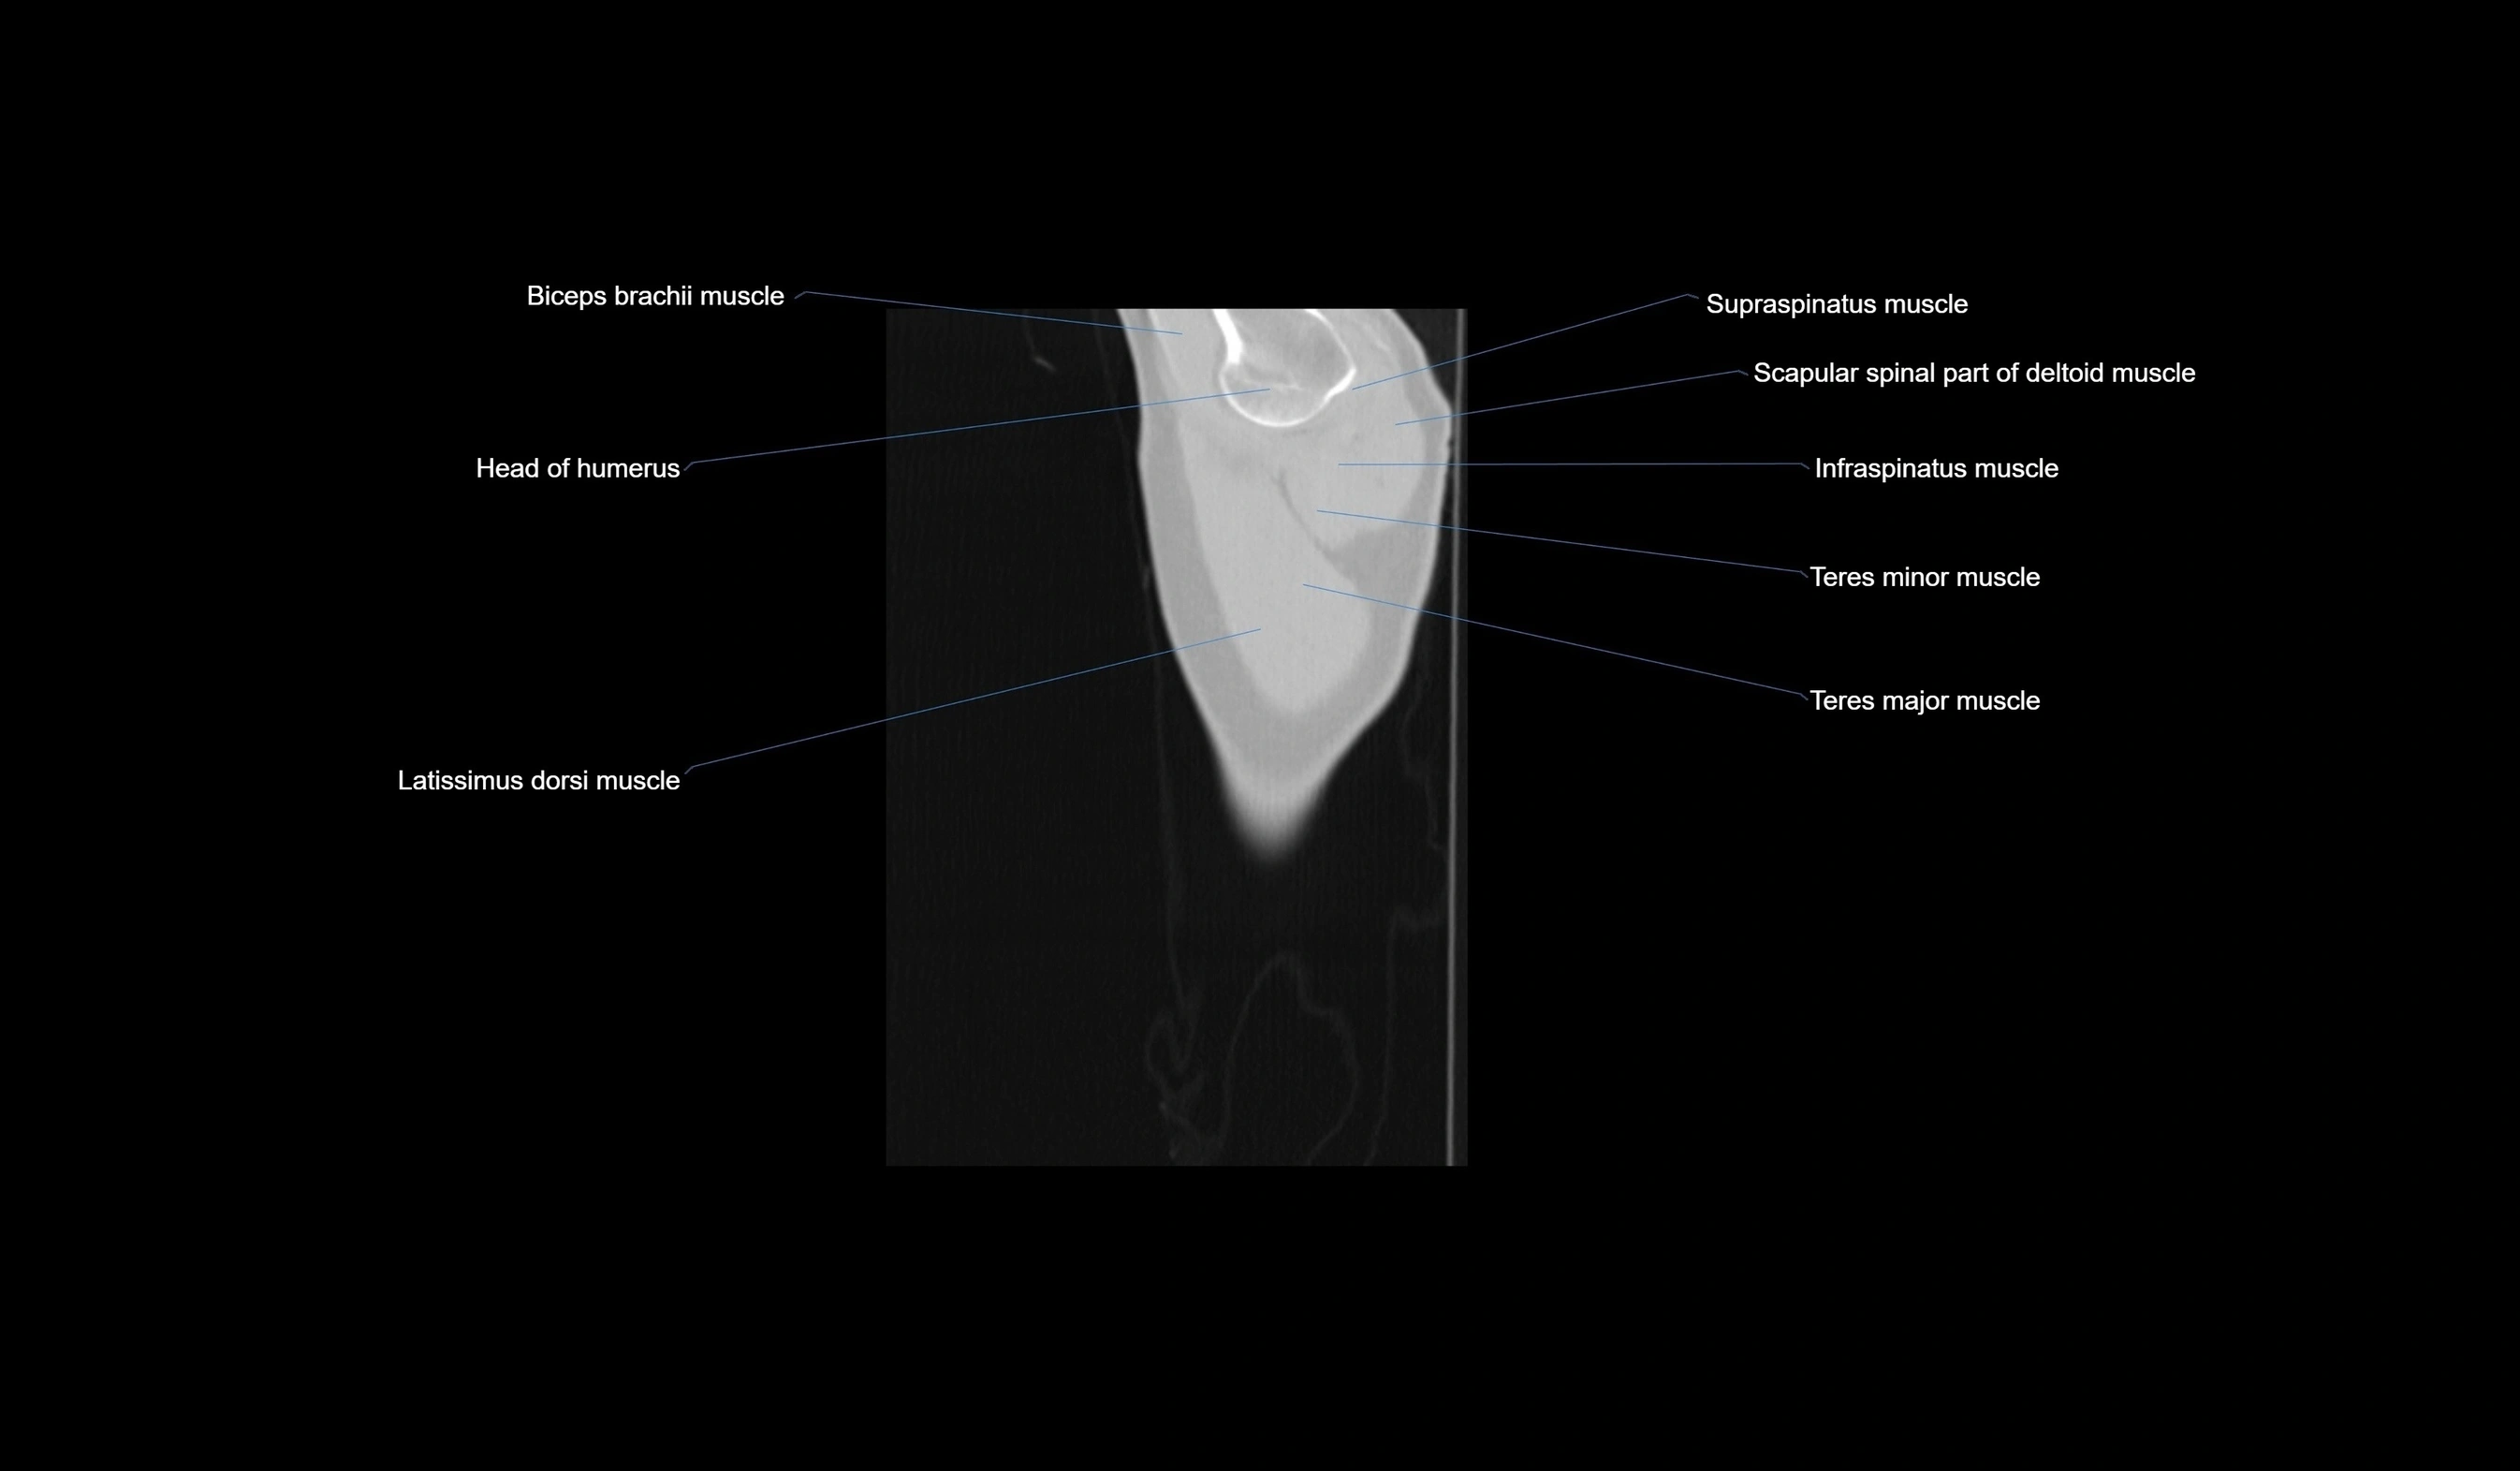

- Biceps brachii muscle

- Head of humerus

- Infraspinatus muscle

- Latissimus dorsi muscle

- Scapular spinal part of deltoid muscle

- Supraspinatus muscle

- Teres major muscle

- Teres minor muscle